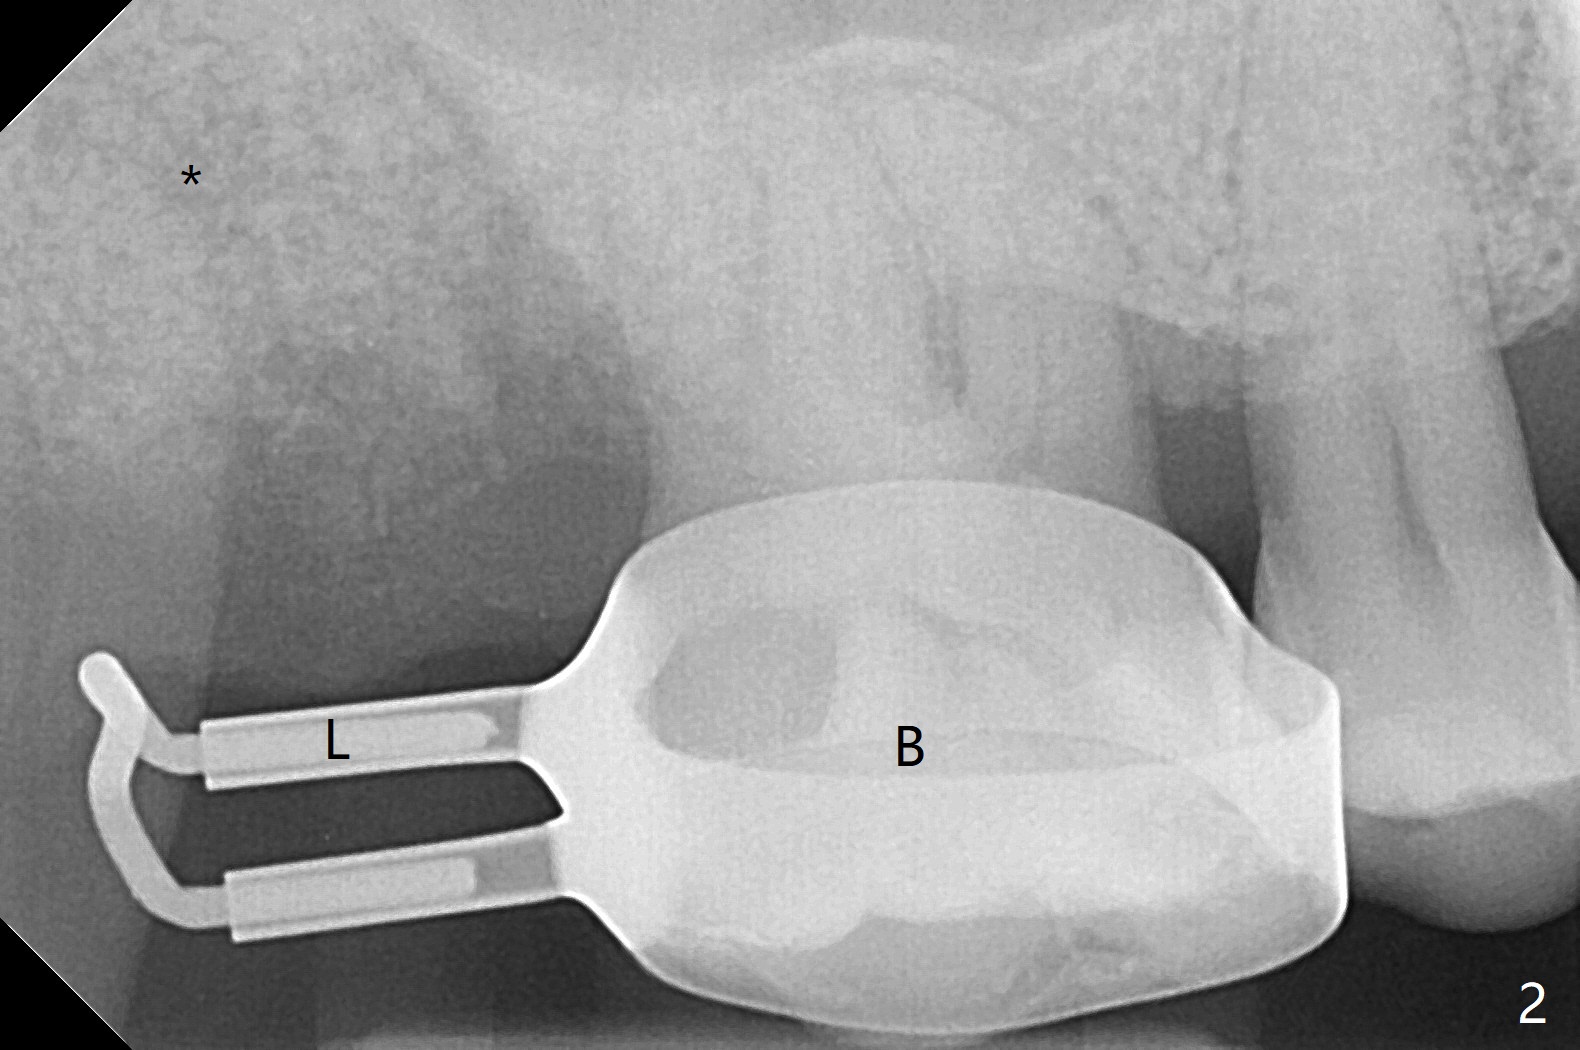

A 55-year-old woman requests extraction of the tooth #2 with pain and mobility a few weeks post SRP (Fig.1) and finally agrees with socket preservation (Fig.2,3 *). In fact the mesiobuccal root appears to have been fractured. She is a heavy bruxer (nuts). There is a large amount of granulation tissue in a large single socket. After suture fixation over Osteogen plug and allograft (*), a prefabricated band (B) and loop (L) are cemented in place. Periodontal dressing is applied mainly underneath the loop for wound protection and bone graft and membrane fixation. The central portion of the periodontal dressing remains in place over the socket opening 1 week postop (Fig.4). The removable distal portion of the loop dislodged 23 days postop. The free end of the fixed mesial portion of the loop is irritating; the patient returns the following day. After removal of the spacer, the socket appears to have healed (Fig.5). No bone graft has been lost (Fig.6 *, as compared to immediately postop (Fig.2,3)). Return to Upper Molar Immediate Implant, Trajectory Xin Wei, DDS, PhD, MS 1st edition 04/13/2019, last revision 01/06/2020